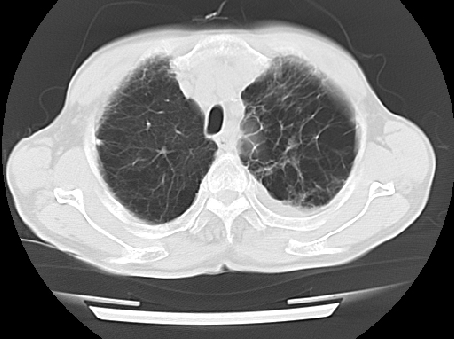

以下是引用ct诊断高手在2009-5-29 13:50:00的发言:[br]考虑左侧中央型肺癌,阻塞性肺炎伴肺不张。纵隔淋巴结转移。慢支 肺间质纤维化肺气肿。左侧胸腔积液。左侧肋骨转移?

以下是引用hhcckk在2009-5-29 14:58:00的发言:[br]左上周围型肺癌,左肺门、纵隔淋巴结转移,左侧胸腔积液,左侧肋骨转移[br]